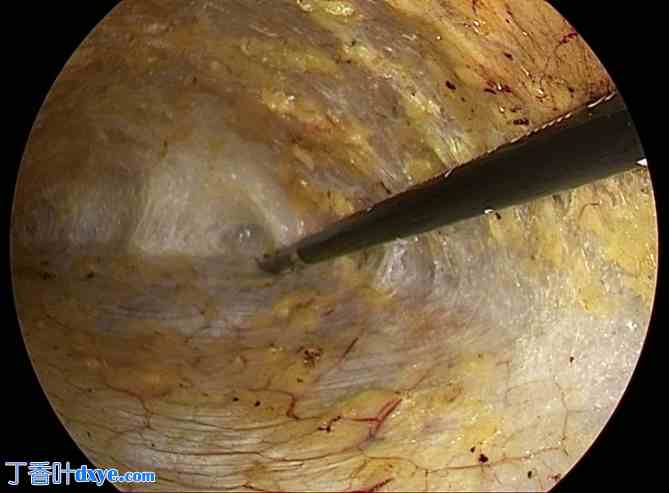

图 7

7.jpg

带倒钩缝合线的针头穿过标记的蓝线。